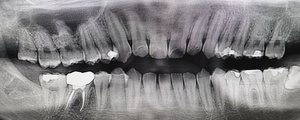

After(下親知らずの抜歯後) 横に生えた状態で埋まっている親知らずの抜歯後 虫歯がある親知らずの抜歯後 抜歯後の骨の状態のレントゲン像

まず、親知らずと骨の中にある神経の位置、歯や周囲の骨の詳細な情報を確認するために、歯科用パノラマデジタル写真で口腔内を撮影します。撮影結果を踏まえ、抜歯方法や施術の難易度をしっかり確認しました。

1年後、取り除いた親知らず周囲の骨がしっかり再生したことを確認しました。